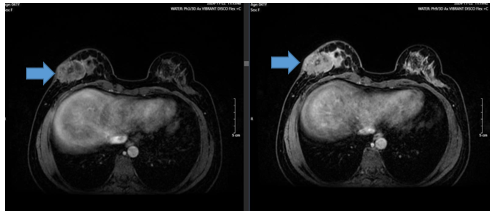

- CT ngực, bụng: Chưa phát hiện bất thường

Hình 5: Hình ảnh CT ngực 13 chu kì điều trị phác đồ TCHP- HP u vú phải đã cắt ( mũi tên xanh) không phát hiện hạch, khối bất thường trên CT ngực

Trong quá trình điều trị bệnh nhân được theo dõi định kì siêu âm tim và điện tim kết quả qua các chu kì theo dõi là bình thường. Xét nghiệm chỉ điểm từ lúc chẩn đoán đến thời điểm hiện tại đều không tăng